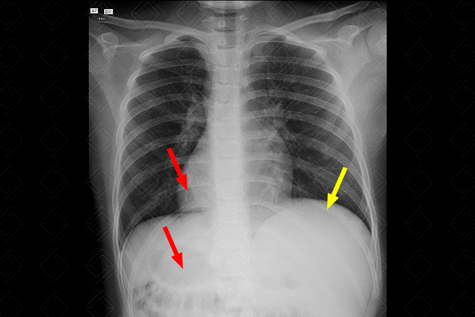

[cms-watermark] Descrição da figura: Radiografia de tórax evidenciando situs inversus totalis , com ápice cardíaco e bolha gástrica voltados para a direita (setas vermelhas). Fígado à esquerda (seta amarela).

Exames de imagem: Em geral, trata-se de achado acidental, podendo ser observado em qualquer exame de imagem. No nosso caso, trata-se de uma radiografia de tórax evidenciando coração à direita, bem como bolha gástrica à direita, por situs inversus totalis .